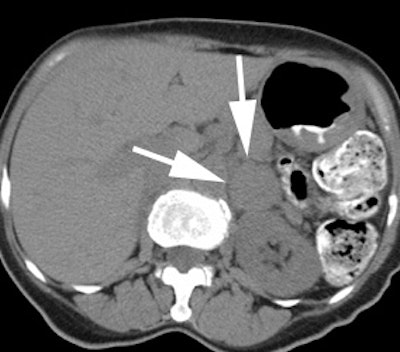

Pheochromocytoma: The patient below was being evaluated for hypertension and abnormally elevated catecholamine levels. CT revealed a mass in the left adrenal gland (white arrows). The 72 hour posterior MIBG image demonstrated abnormal tracer accumulation in this lesion (black arrows) consistent with a pheochromocytoma. Physiologic hepatic activity can be seen in the right upper abdomen. |